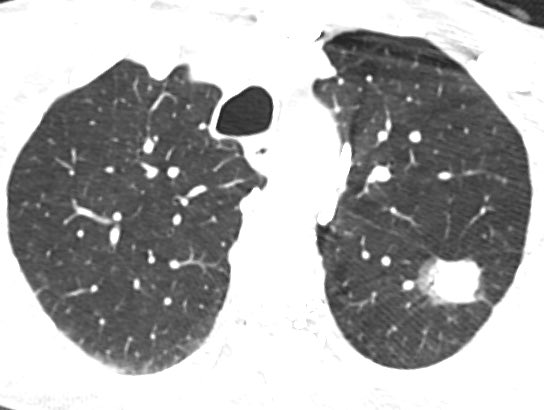

80 y/o patient presenting w/ headache is found to have a pineal mass and hydrocephalus. What is the most likely diagnosis and cause of the hydrocephalus?